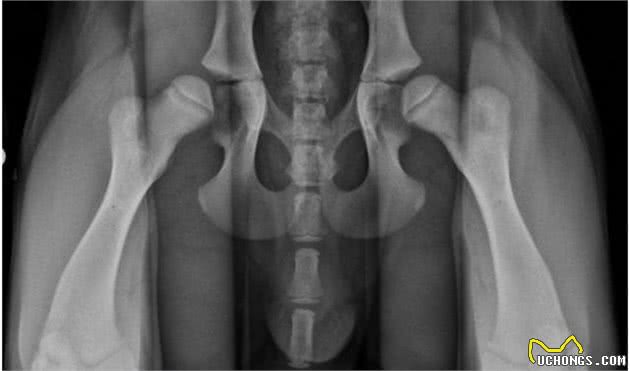

3.狗狗关节发育不良引起

狗也容易患髋关节和肘关节发育不良。虽然有些狗更容易遗传这种疾病,但基本上所有的狗都能看到这种症状。这种类型的发育不良会导致肘部或臀部畸形,这会使狗的坐姿或行走姿势非常奇怪。髋关节和肘关节发育不良也可以是轻度或重度。这种疾病,如果有症状,在狗比较小的时候就可以发现,并且可以通过手术使狗自由康复;如果没有手术干预,这种疾病会伴随狗一生,并会影响狗后期的正常生活。